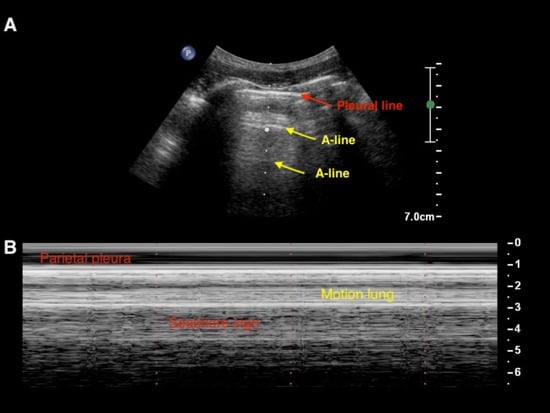

Artifacts

Real Images